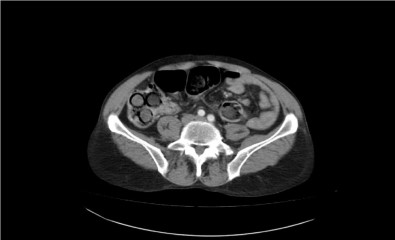

Polis, şahsın midesinde eroin olabileceğinden şüphelenip hemen hastanenin gastroenteroloji bölümüne götürdü. Burada tomografisi çekilen midede, sosis büyüklüğünde paketler tespit edildi. Ancak polis, emin olmak için daha sonra şahsa endoskopi işlemi de yaptırdı. Bu sayede ucunda ışıklı küçük bir kamera bulunan ve endoskopi adı verilen bir cihaz yardımıyla şahsın yemek borusu, mide, onikiparmak bağırsağı ve kalın bağırsaklarında 49 paket sosis büyüklüğünde paketler olduğu kesinleşti.